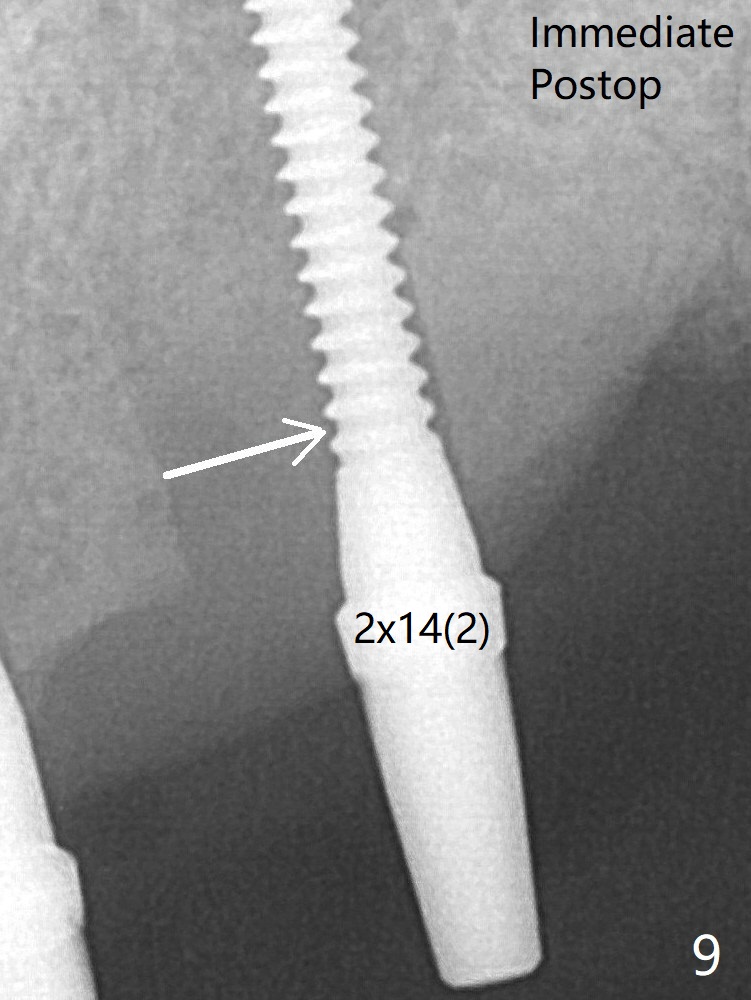

A 2x14(2) mm 1-piece implant is placed at #10 site after change in osteotomy position (Fig.9 arrow), which leaves a concavity mesial to #10 two and a half years later (Fig.22, 42) with 2-3 thread exposure. It would be ideal to place an implant with 4 mm cuff deeper by 2 mm.